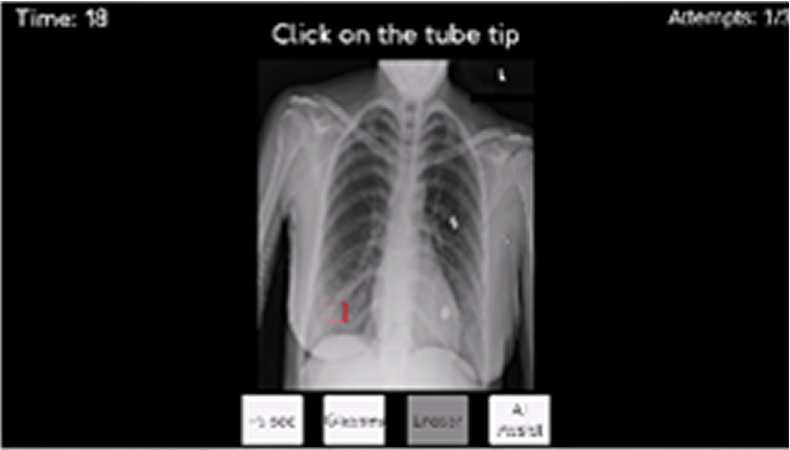

Recognizing normal/abnormal positioning of lines and tubes and their tips to teach accurate image interpretation

Recognizing normal/abnormal positioning of lines and tubes and their tips with answers derived from the AI attention heat map of a deep learning model